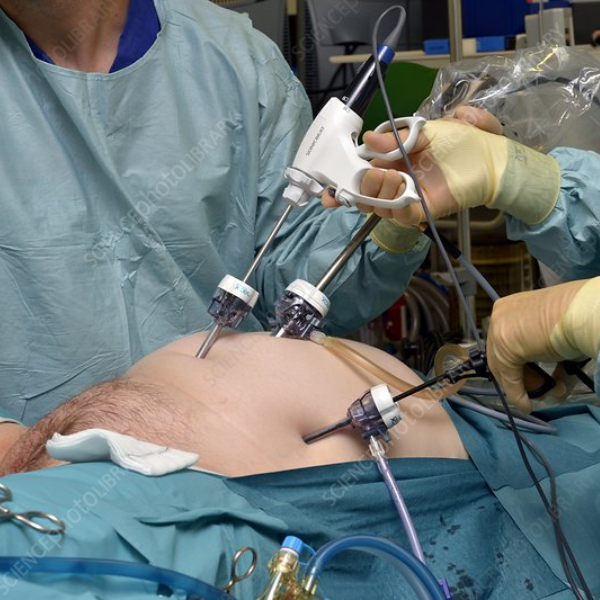

laparoscopy

Minimally invasive surgical care offering faster recovery, reduced pain, and precise treatment for abdominal and pelvic conditions.

Services & procedures available.

Advanced minimally invasive surgeries ensuring faster recovery, less pain, and improved surgical outcomes for abdominal and pelvic conditions.

1.Laparoscopic Cholecystectomy (Gallbladder Removal)

Small-incision surgery removing gallbladder stones with minimal pain and quicker recovery.

02. Laparoscopic Appendectomy

Safe, minimally invasive removal of an inflamed appendix reducing complications and healing time.

03. Laparoscopic Hernia Repair

Mesh-based repair performed through tiny incisions for faster movement and reduced postoperative discomfort.